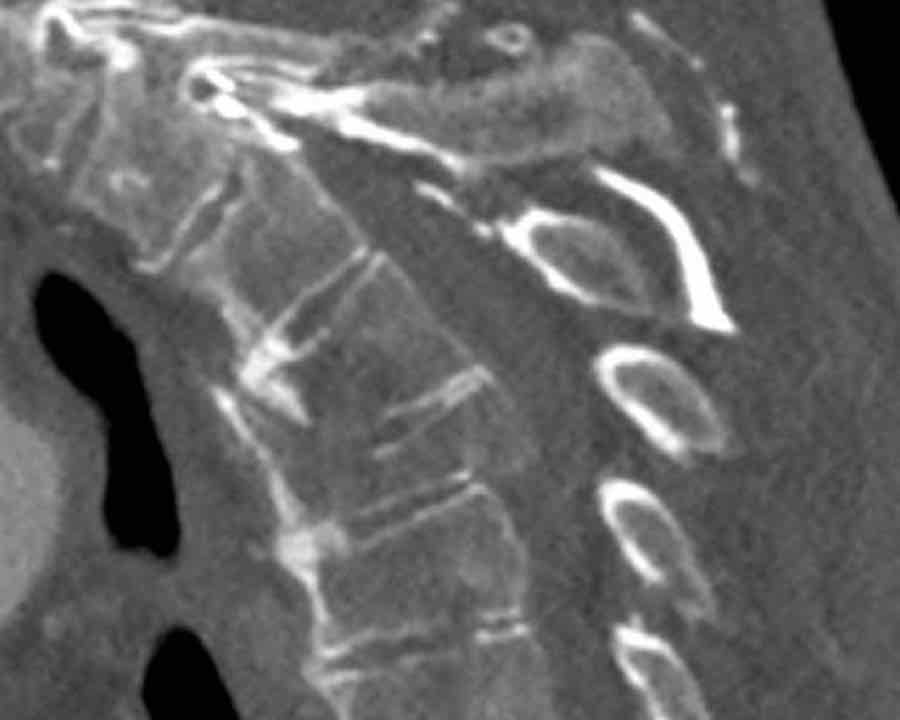

What are the findings?

What is the highest AO-type of injury?

Findings

- Dislocation of the proximal vertebrae anteriorly (white arrow).

- Both facet joints are perched (black arrows). Perched means to be situated above or on the edge of something. In this case the inferior process of vertebral articular joints appears to sit on the ipsilateral superior articular process of the vertebra below.

- Due to the anterior displacement a fracture of the spinous process is seen, in a horizontal oblique course.

Conclusion

Type C injury.